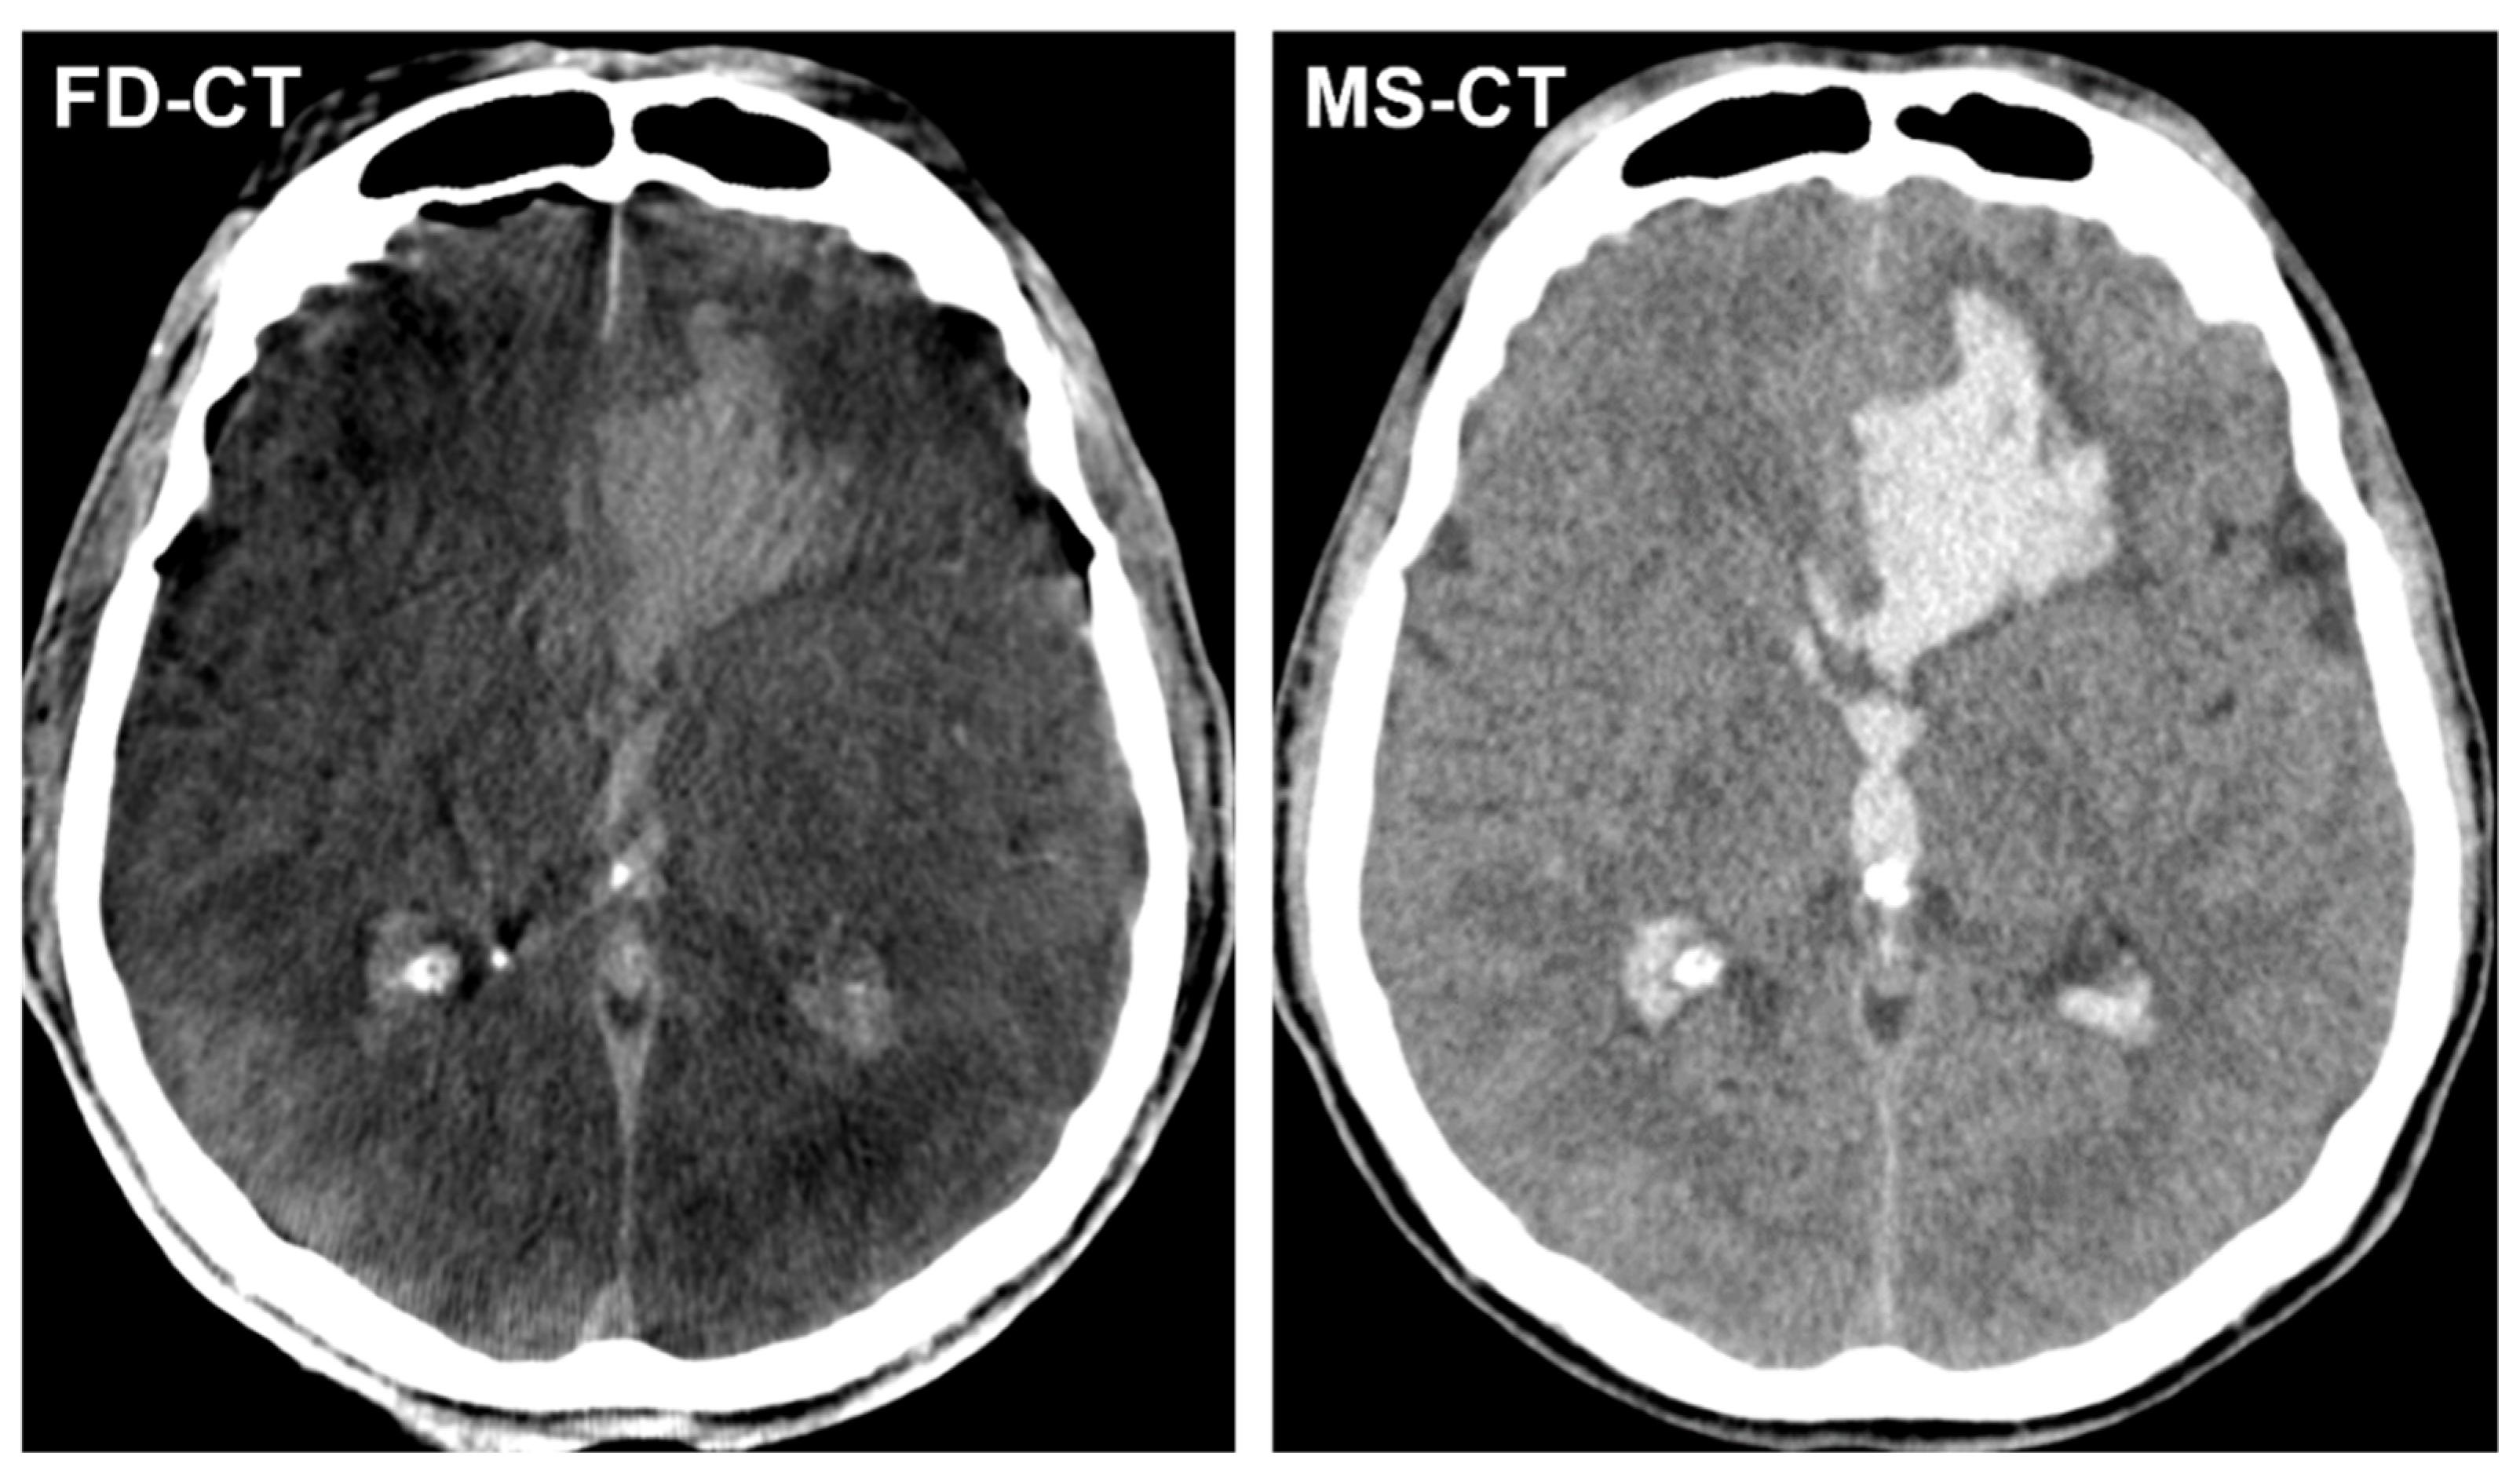

3.3.1. Blood Distribution

3.4.2. Modified Graeb Score